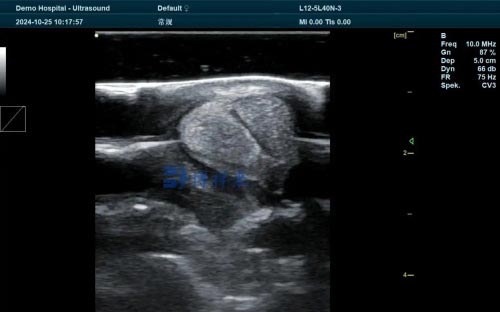

B‑mode imaging: At 20–28 days post‑insemination, the fluid‑filled uterus, heartbeat, and embryo sac can be detected reliably .

Doppler imaging: By assessing luteal blood flow at around day 20, practitioners can differentiate pregnant from non‑pregnant animals—achieving ~86–93% accuracy.

Portable veterinary units (5–9 MHz transducers) provide adequate resolution for uterine Structures; 5 MHz offers depth, 7.5 MHz greater clarity.